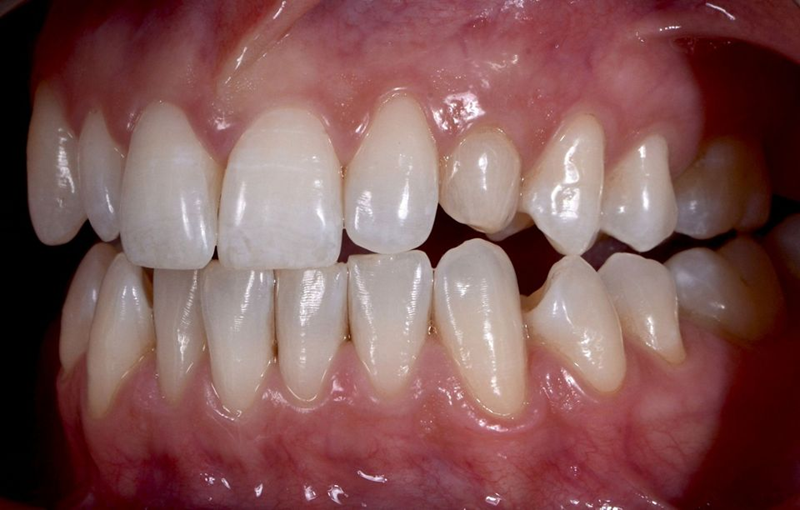

口外检查中,面部评价显示面部对称、比例匀称。微笑分析显示中线矢状面与微笑中线重合,上切牙和尖牙的暴露率为90%(图1)。微笑还显示侧切牙形状不同,与对侧恒尖牙相比,左上乳尖牙更短、更窄、颜色更黄(图2-4)。

口内检查中,乳牙处可见大量角质化牙龈,整体口腔卫生状况良好(图5-7)。

Fig. 5: Intraoral frontal view

Fig. 6: Intraoral view: The discrepancy between upper canines and lateral incisors is clear. Note that the deciduous tooth is shorter than the contralateral, both at the occlusal and at the gingival side.

Fig. 7: Magnification of the deciduous tooth: A wide amount of keratinized gingiva is shown.

功能分析显示尖牙引导由侧切牙和第一前磨牙提供,而乳尖牙不受影响(图8)。